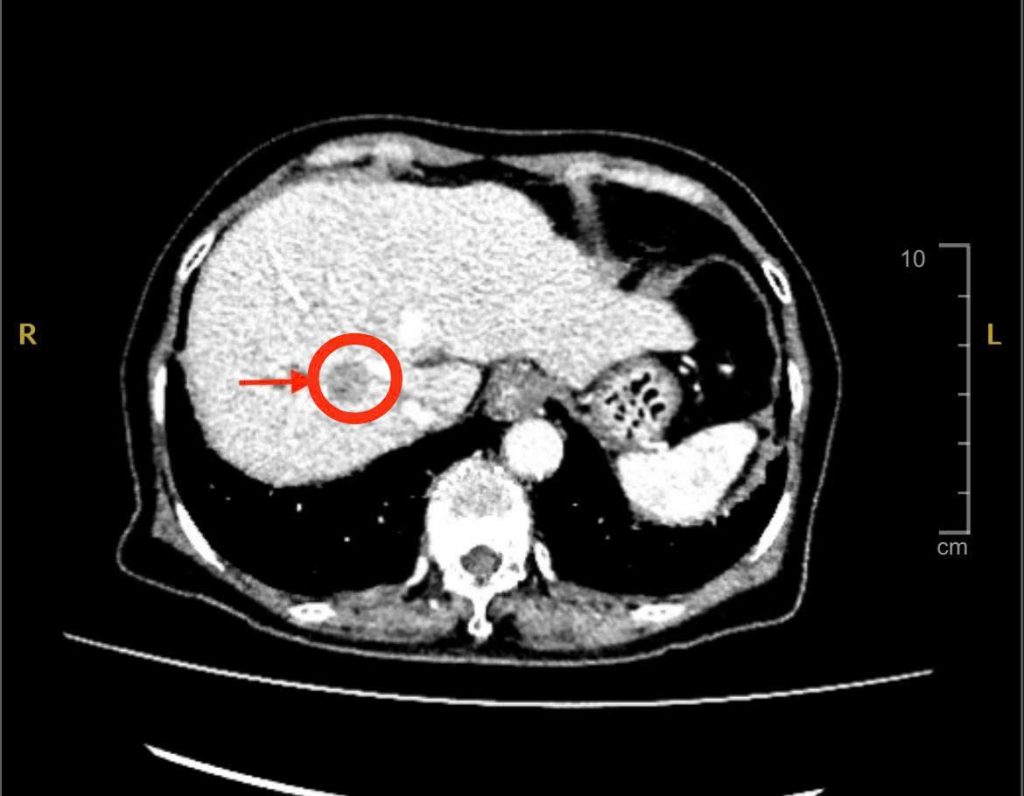

Với tiền sử bệnh xơ gan đang theo dõi và điều trị, xơ gan lại là yếu tố nguy cơ cao của ung thư gan, các bác sĩ nghi ngờ đây có thể là dấu hiệu đầu tiên của bệnh. Vì thế, bác sĩ chỉ định bà siêu âm bụng và chụp MSCT thì phát hiện có khối u gan bên phải với kích thước khoảng 2cm, nghĩ nhiều đến ung thư nguyên phát tế bào gan (HCC) – một dạng ung thư gan phổ biến ở người có bệnh nền xơ gan, viêm gan B hoặc viêm gan C.

Hình ảnh CT khối u gan

Trong quá trình mổ, ê – kíp các bác sĩ khoa Ngoại Tiêu Hóa Gan Mật Tụy đã thám sát và phát hiện khối u có kích thước chỉ khoảng 2cm. Tuy nhiên, khối u không nằm trên bề mặt mà nằm sâu trong nhu mô gan, ở vị trí rất sát mạch máu lớn ở gan. Vì thế, các bác sĩ phải sử dụng siêu âm trong mổ để xác định chính xác vị trí khối u và khống chế tất cả các mạch máu lớn nuôi gan, tránh chảy máu ồ ạt.